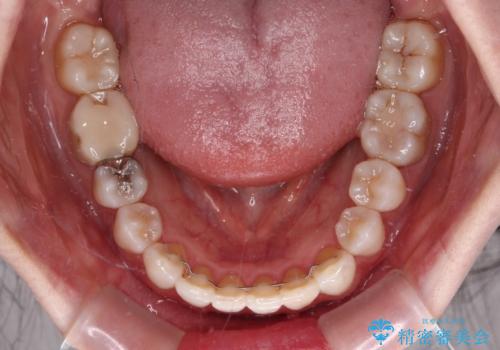

骨格的な左右差があったため、上下の正中を合わせることができませんでした。

骨格の差は改善できないため、奥歯の咬み合わせに物足りなさを感じましたが、奥歯の咬み合わせによる不自由はなく、口元の突出感も改善することができました。